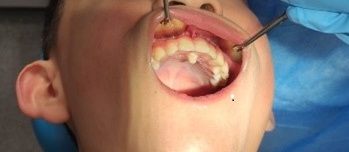

Paciente varón de 6 años, sin antecedentes familiares ni personales de interés, que acude a la consulta de Pediatría para la revisión de 6 años, donde se observan múltiples caries y se deriva a la consulta de Odontología. En la exploración intraoral presentaba los incisivos centrales superiores parcialmente erupcionados con el 21 rotado, diastema interincisivo y ausencia de 62 y sin espacio para la erupción de 22 (Fig. 1). En la línea media por palatino se aprecia la erupción parcial de diente conoide con la presunción de diente supernumerario mesiodens que no presenta movilidad; en oclusión se aprecia mordida cruzada de dicho supernumerario que mantiene incisivos inferiores vestibulizados (clase I molar). Se solicitó una ortopantomografía para valorar la posición y el estado de la erupción de los incisivos superiores, así como descartar presencia de otros supernumerarios o agenesias. La radiografía mostraba la presencia de un diente supernumerario mesiodens en la línea media (Fig. 2). Se hallaba en posición vertical y presentaba una forma conoide. Provocaba un gran diastema interincisal e impedía la correcta erupción de los incisivos centrales y laterales superiores, incluso alterando la oclusión y correcta posición de incisivos inferiores. Se informó a la madre de la necesidad de realizar la extracción para la correcta erupción dentaria del sector anterior y, dada la colaboración del paciente, se realiza en la consulta con anestesia tópica y posteriormente infiltrativa, procediendo a la extracción del mismo (Fig. 3). En la extracción se observa lesión periapical compatible con quiste folicular que se envía al Servicio de Anatomía Patológica para su estudio. El paciente precisará controles periódicos para controlar la erupción dentaria y valorar la necesidad de un tratamiento ortodóncico posterior para cerrar el diastema interincisal y permitir, además, la erupción de los incisivos laterales superiores.

| Figura 2. Ortopantomografía. Se observa un único diente supernumerario en posición vertical situado en palatino en relación con el tercio apical de la raíz del 21. No se observan otros supernumerarios, no hay agenesias y se observan múltiples caries en dentición temporal |